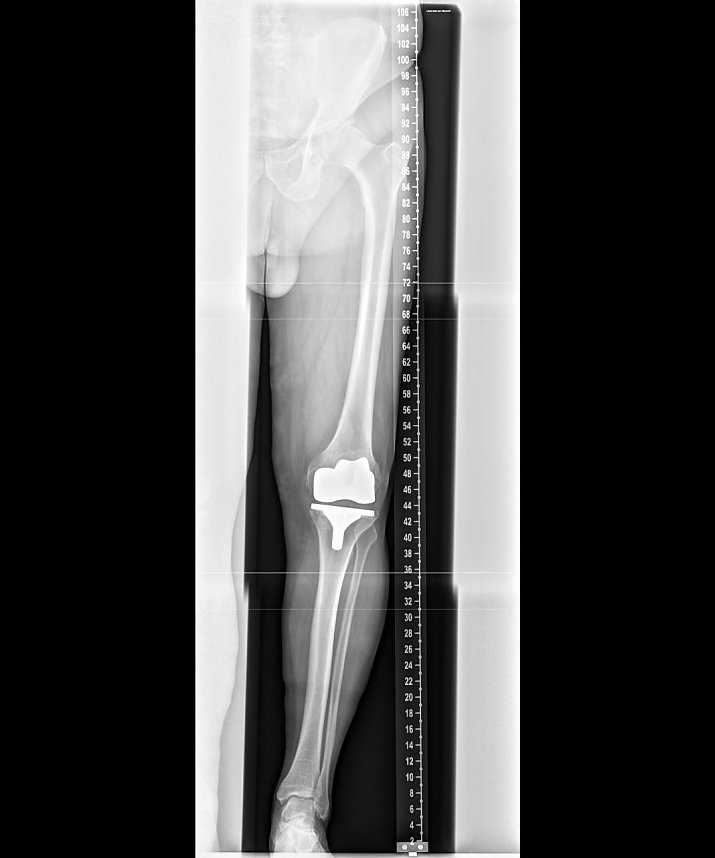

Ganzbeinaufnahme mit dem direkt-digitalen Stitching (Foto: SHK)